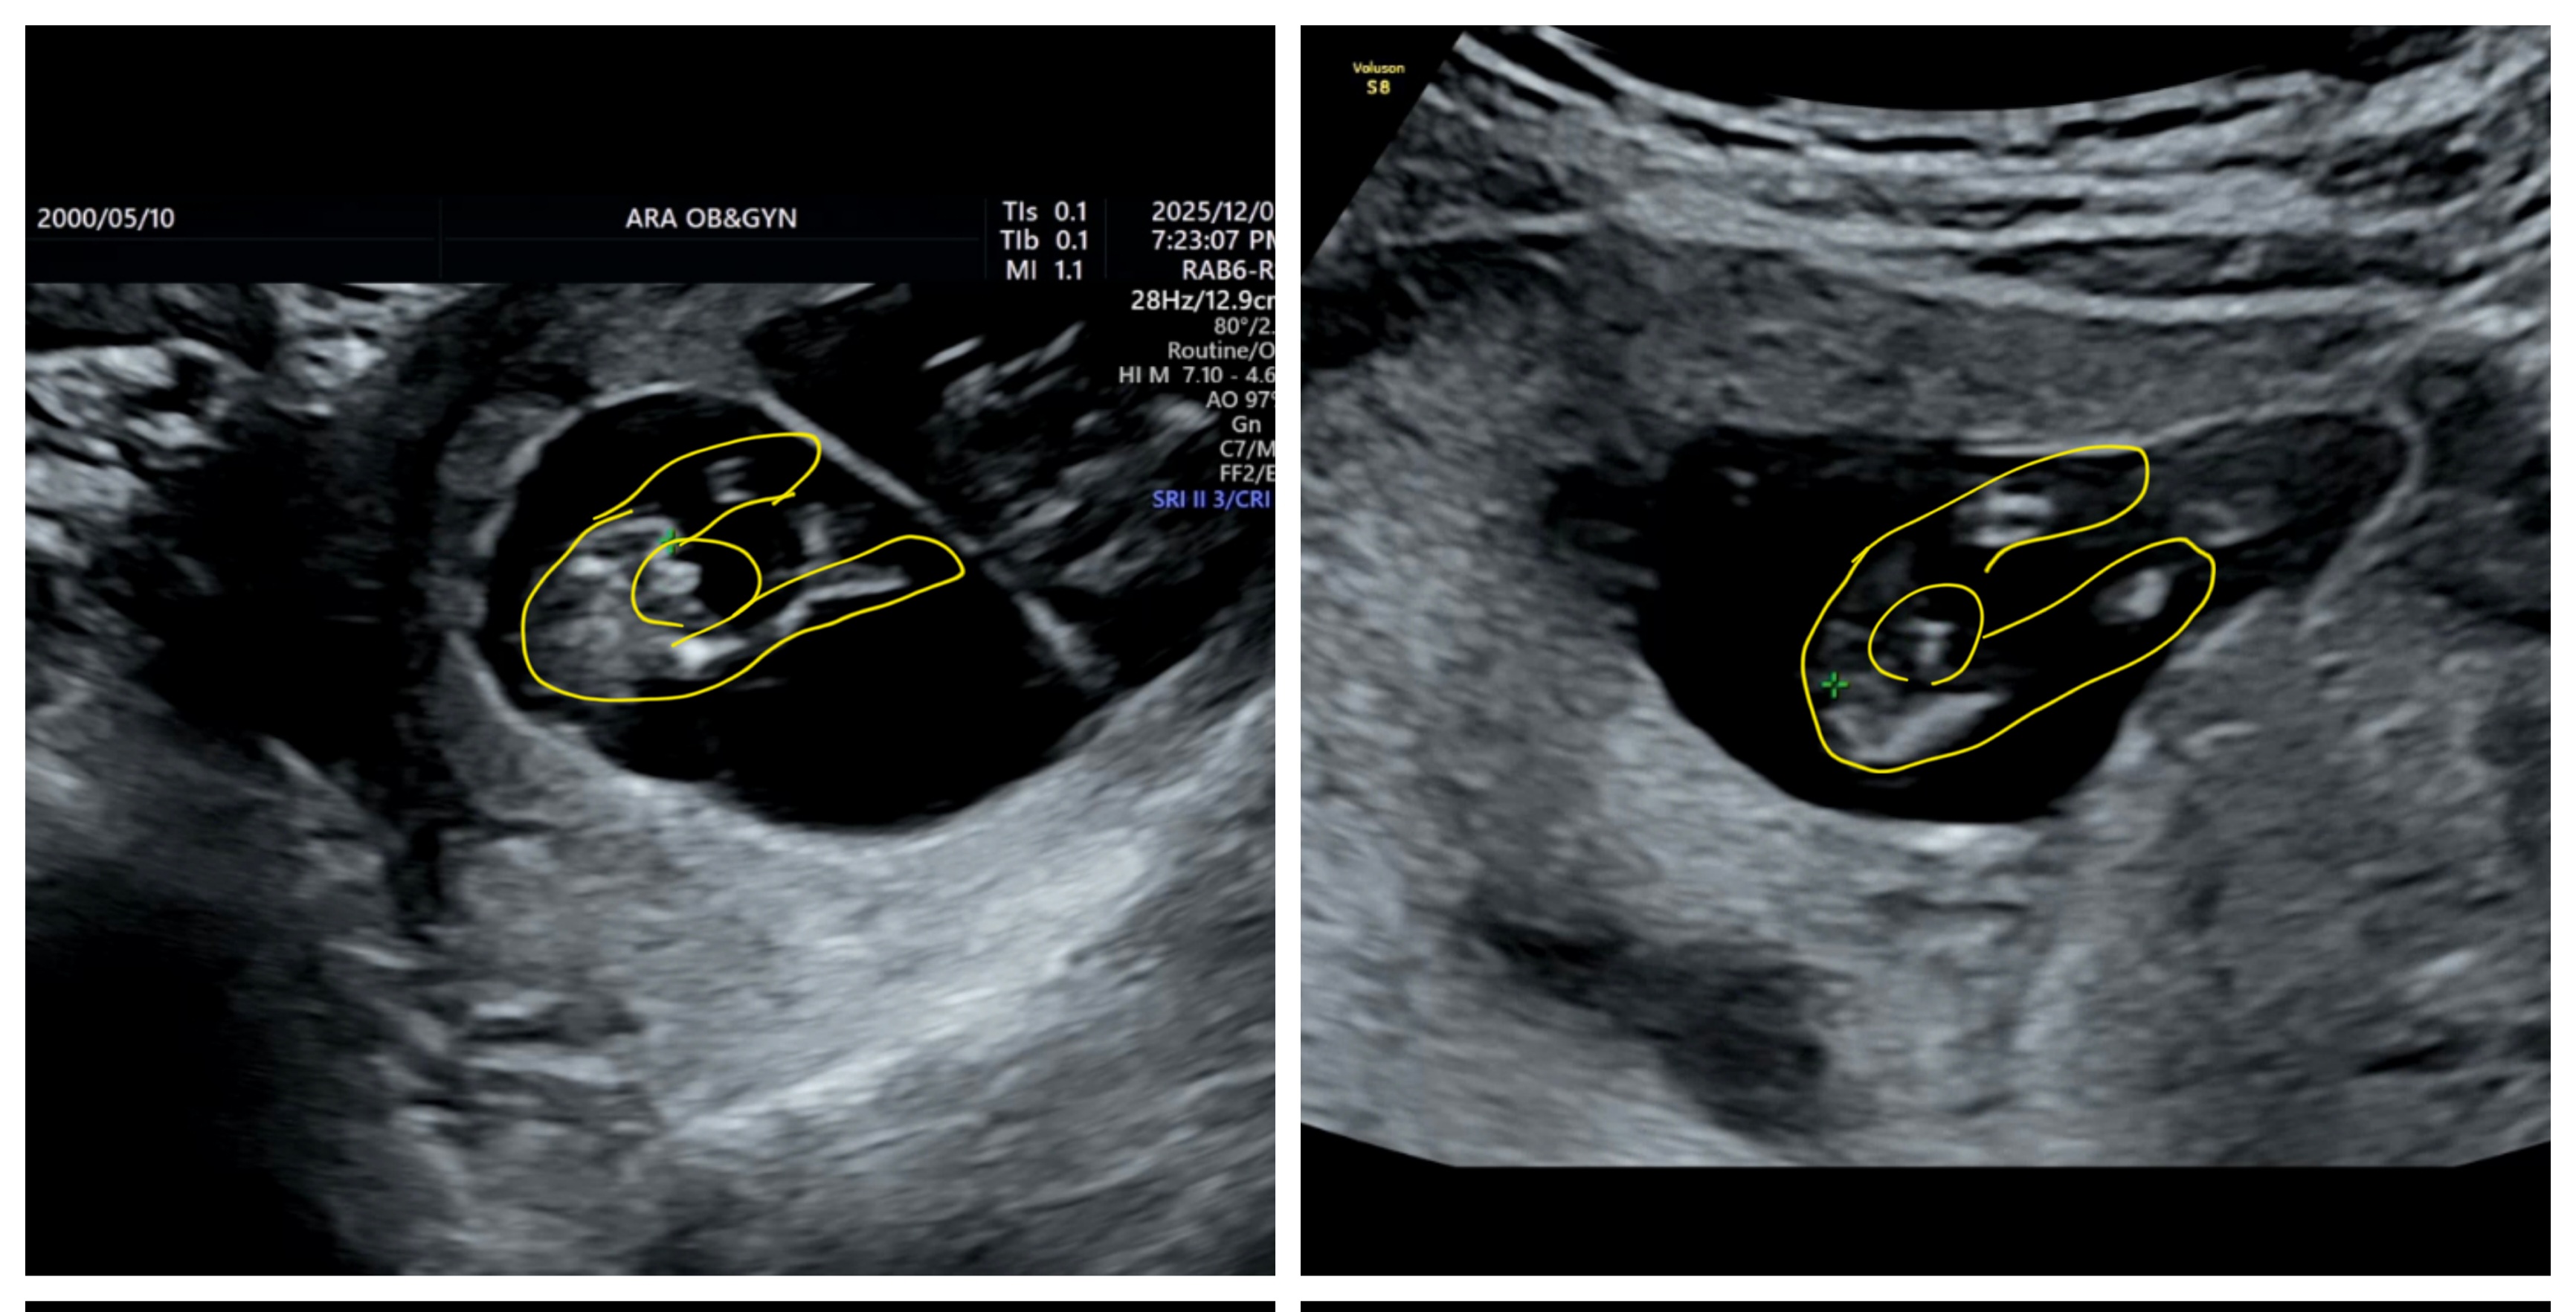

초음파 성별 한번 봐주세용

11주 3일에 니프티 결과 y염색체 있다고 나와서 둥이 중에 한명 이상은 아들인데 쌤이 초음파 보시고 둘다 아들 같다고 하셨는데 아들둥이 일까요?? 아님 아직 너무 일러서 모를까요?? 아들들은 빨리 안다는 사람들도 있던데 알려주세용